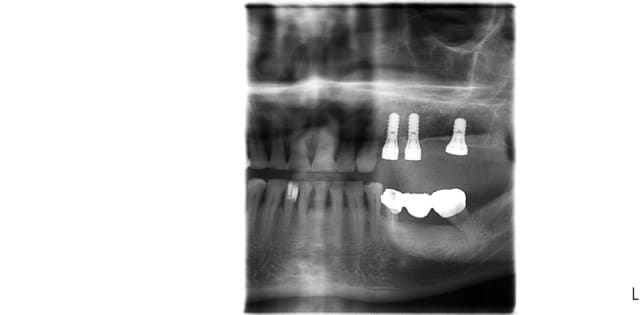

voici mon premier cas d'Extraction implantation Immediate...

bien sur toute la ligne! sauf positionnement de 24 en palatin

> bien sur toute la ligne! sauf positionnement de 24 en palatin

bof, allez, peut être de 0.5mm trop palatin...pas toujours évident à faire quand l'alvéole "aspire" naturellement les forets...

amha çà va pas changer grand chose pour la prothèse...et puis au moins il n'aura pas le risque de corticale vestibulaire trop fine...

En examinant la paroi vestibulaire de l’alvéole après extraction...j'ai pensé que la résorption faisant l'option implantaire serait plus compliquée par la suite. J'ai donc posé l'implant en 24;

A posteriori je me dit que j'aurai du poser la membrane autour de l'implant pour éviter la compétition cellulaire et optimiser mon comblement.

oui, la pano date du jour de la consult,

on a fait un assainissement paro et d' autres soins on été entrepris entre temps.